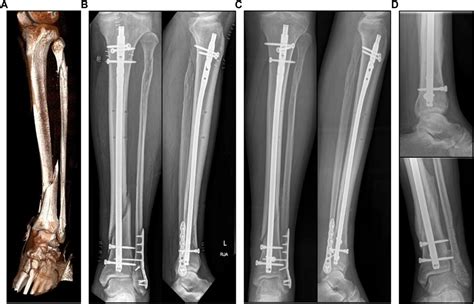

Frontiers | Simulation-based prediction of bone healing and treatment ...